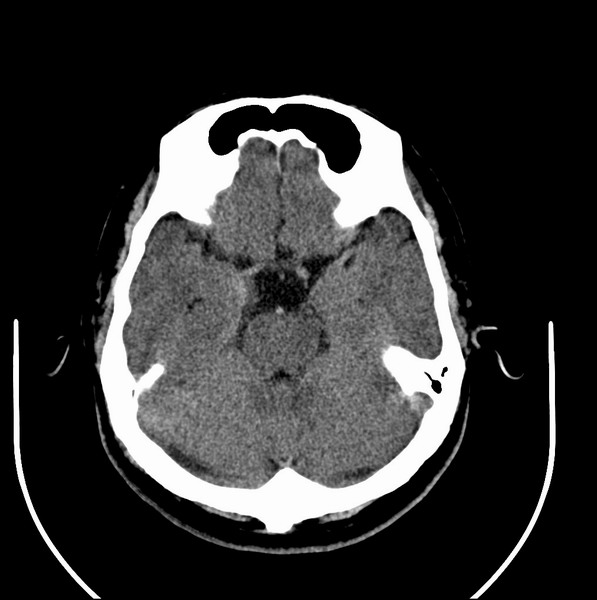

扫描示鼻咽腔不对称,中度狭窄,右侧咽隐窝消失,局部软组织肿块,鼻咽右侧壁增厚形成肿块,突入鼻咽腔,肿块平扫呈等密度,肿块向深部侵润,右侧翼内外肌受侵,右侧咽旁间隙变窄;向后生长,头长肌界线欠清,向后上生长侵犯同侧颈动脉鞘区。双侧海绵窦增宽,内见软组织影与鼻咽部肿块相连。考虑鼻咽癌。鼻咽癌主要是放射治疗,且效果较好;到当地有治疗设备较大医院治疗即可。

这个病例有点特殊,和常见的鼻咽癌不太一样,以向颅内侵犯为主,骨质破坏区小。鼻咽癌首先要考虑,有没有其他可能?本人不会看mr片,期待有人能讲解,期待病理。

鼻咽部新生物(纤维血管瘤?鼻咽癌?)侵犯右侧中颅窝底及右侧海绵窦;建议必要时活检定性。

典型鼻咽癌侵犯右侧海绵窦(对放疗敏感)